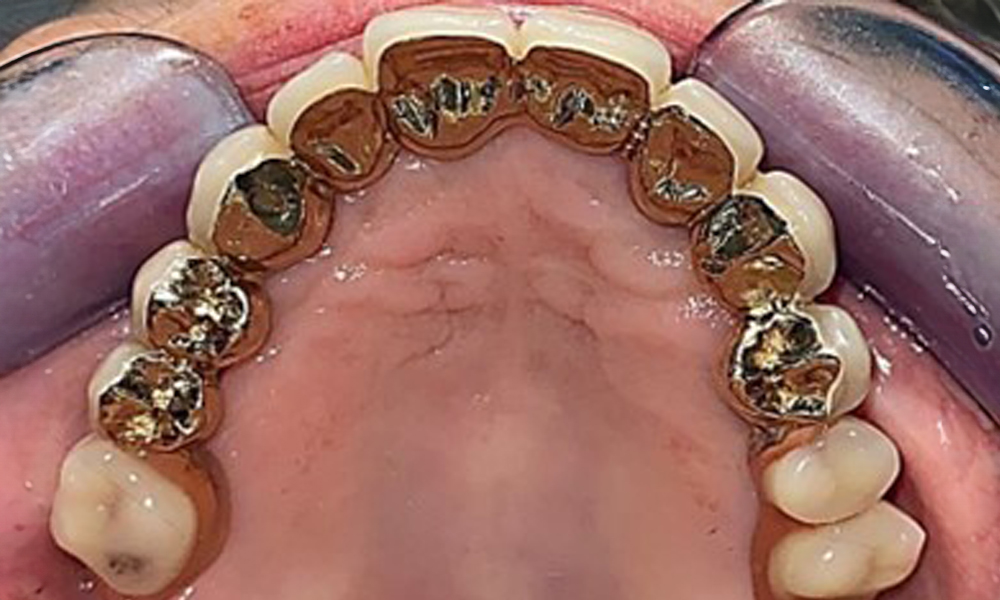

Occlusal view: Maxilla with tooth and implant-supported telescopic prostheses.

Fig. 2: Occlusal view: Maxilla with tooth and implant-supported telescopic prostheses

The dental findings are as follows: Combined removable implant and tooth-supported telescopic prostheses on implants 15, 13, 21, 23, 24, 25 and tooth 11 (Fig. 1, Fig. 2, Fig. 3). The patient was fitted with a fixed mandibular denture. Adequate bridges were present over 37 to 34 and 45 to 47 (Fig. 4), the crown margins were intact and there were no active caries. A composite filling with a marginal gap was present on tooth 43. There was mandibular gingival recession, exposing 1 to 3 mm of root surface. This also applies to 11.

The patient was fitted with a combined removable maxillary telescopic prosthesis more than 25 years ago (Fig. 1, Fig. 2, Fig. 3) and is very happy with her dentures. The patient has an adequate fixed denture for the mandible (Fig. 4).